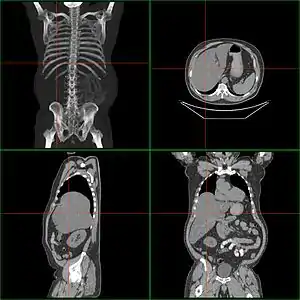

| Computerized tomography of hepatomegaly | |

Computerized tomography (CT) can help to obtain accurate anatomical information, in individuals with hepatomegaly for the purpose of a complete diagnosis.[21]